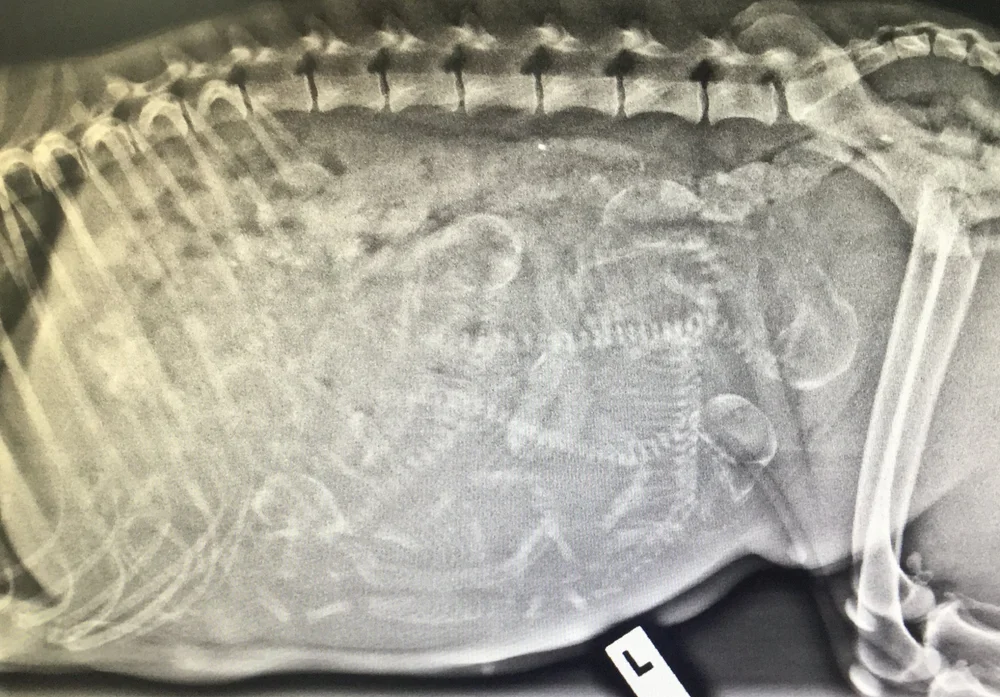

A 50 day pregnant dog xray shows the development of embryos. Cammies is our German Shorthaired Pointer and she is having her first litter of puppies.

Looking again at the X Rays it kinda looks like 7-8 puppies.

March 27 2020 3 Comments. 50 Days Pregnant Dog Xray. X-rays most often give us an exact count of the litter but even with the best images some puppies could be hiding behind another puppy or the dams spine.

This is my girls 3rd litter and the prior litters were large 11 and 13 and came on days 61 and 59 respectively. It takes about 45 days for the puppies bones to mineralize in the uterus meaning they cannot be seen on x-ray before this point. Gary - Purebred Mutt.

Judys due any day now so we decided to get an x-ray taken to see how many pups she is carrying. As well as eye testing for both breeds to ensure they. Fetal Count Radiography is a commonly-performed procedure that allows both veterinarian and pet owner to know how many puppies or kittens are expected in a pregnancy.

X-rays most often give us an exact count of the litter but even with the best images some puppies could be hiding behind another puppy or the dams spine. X-rays can distinguish between pregnancy false pregnancy and thickening of the uterus in dogs and are the most accurate estimate of litter size. X-rays most often give us an exact count of the litter but even with the best images some puppies could be hiding behind another puppy or the dams.